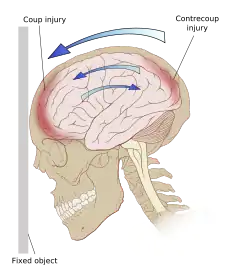

Damage may occur directly under the site of impact, or it may occur on the side opposite the impact (coup and contrecoup injury, respectively).[66] When a moving object impacts the stationary head, coup injuries are typical,[68] while contrecoup injuries are usually produced when the moving head strikes a stationary object.[69]